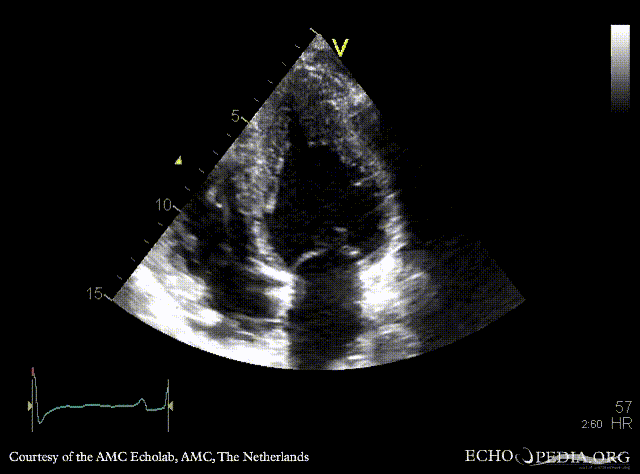

Case 42